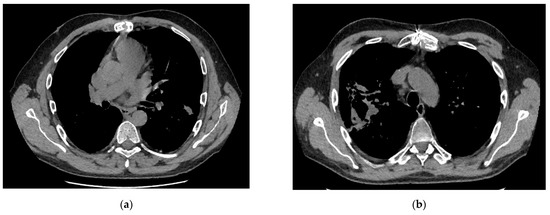

3.4. Laboratory Results, Clinical Symptoms and CT Scan Analysis

| CT scan: | |||

| Segment involved | 3.5 [2–7] | 2 [2–7.25] | 0.960 |

| Left lobe | 1.5 [1–4] | 2 [1.5–2.25] | 0.736 |

| Right lobe | 2.5 [2–3] | 2 [0–4.5] | 0.904 |

| Findings: | |||

| Consolidations | 6 | 2 | 0.464 |

| Nodules | 4 | 6 | |

| Small | 1 | 1 | 0.7469 |

| Large | 3 | 5 | 0.747 |

| Parabronchial infiltrate | 1 | 1 | 0.591 |

| Crescent sign | 3 | 4 | 0.067 |